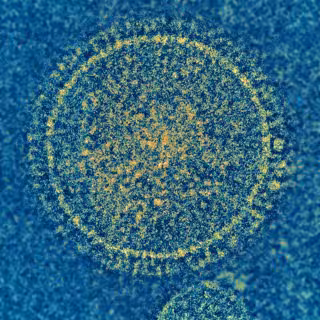

Archivo - El virus sincitial respiratorio (VSR) es el responsable de una enfermedad común de la infancia. No hay vacuna para prevenir la infección por VRS.

Archivo - El virus sincitial respiratorio (VSR) es el responsable de una enfermedad común de la infancia. No hay vacuna para prevenir la infección por VRS. - NIAID - Archivo